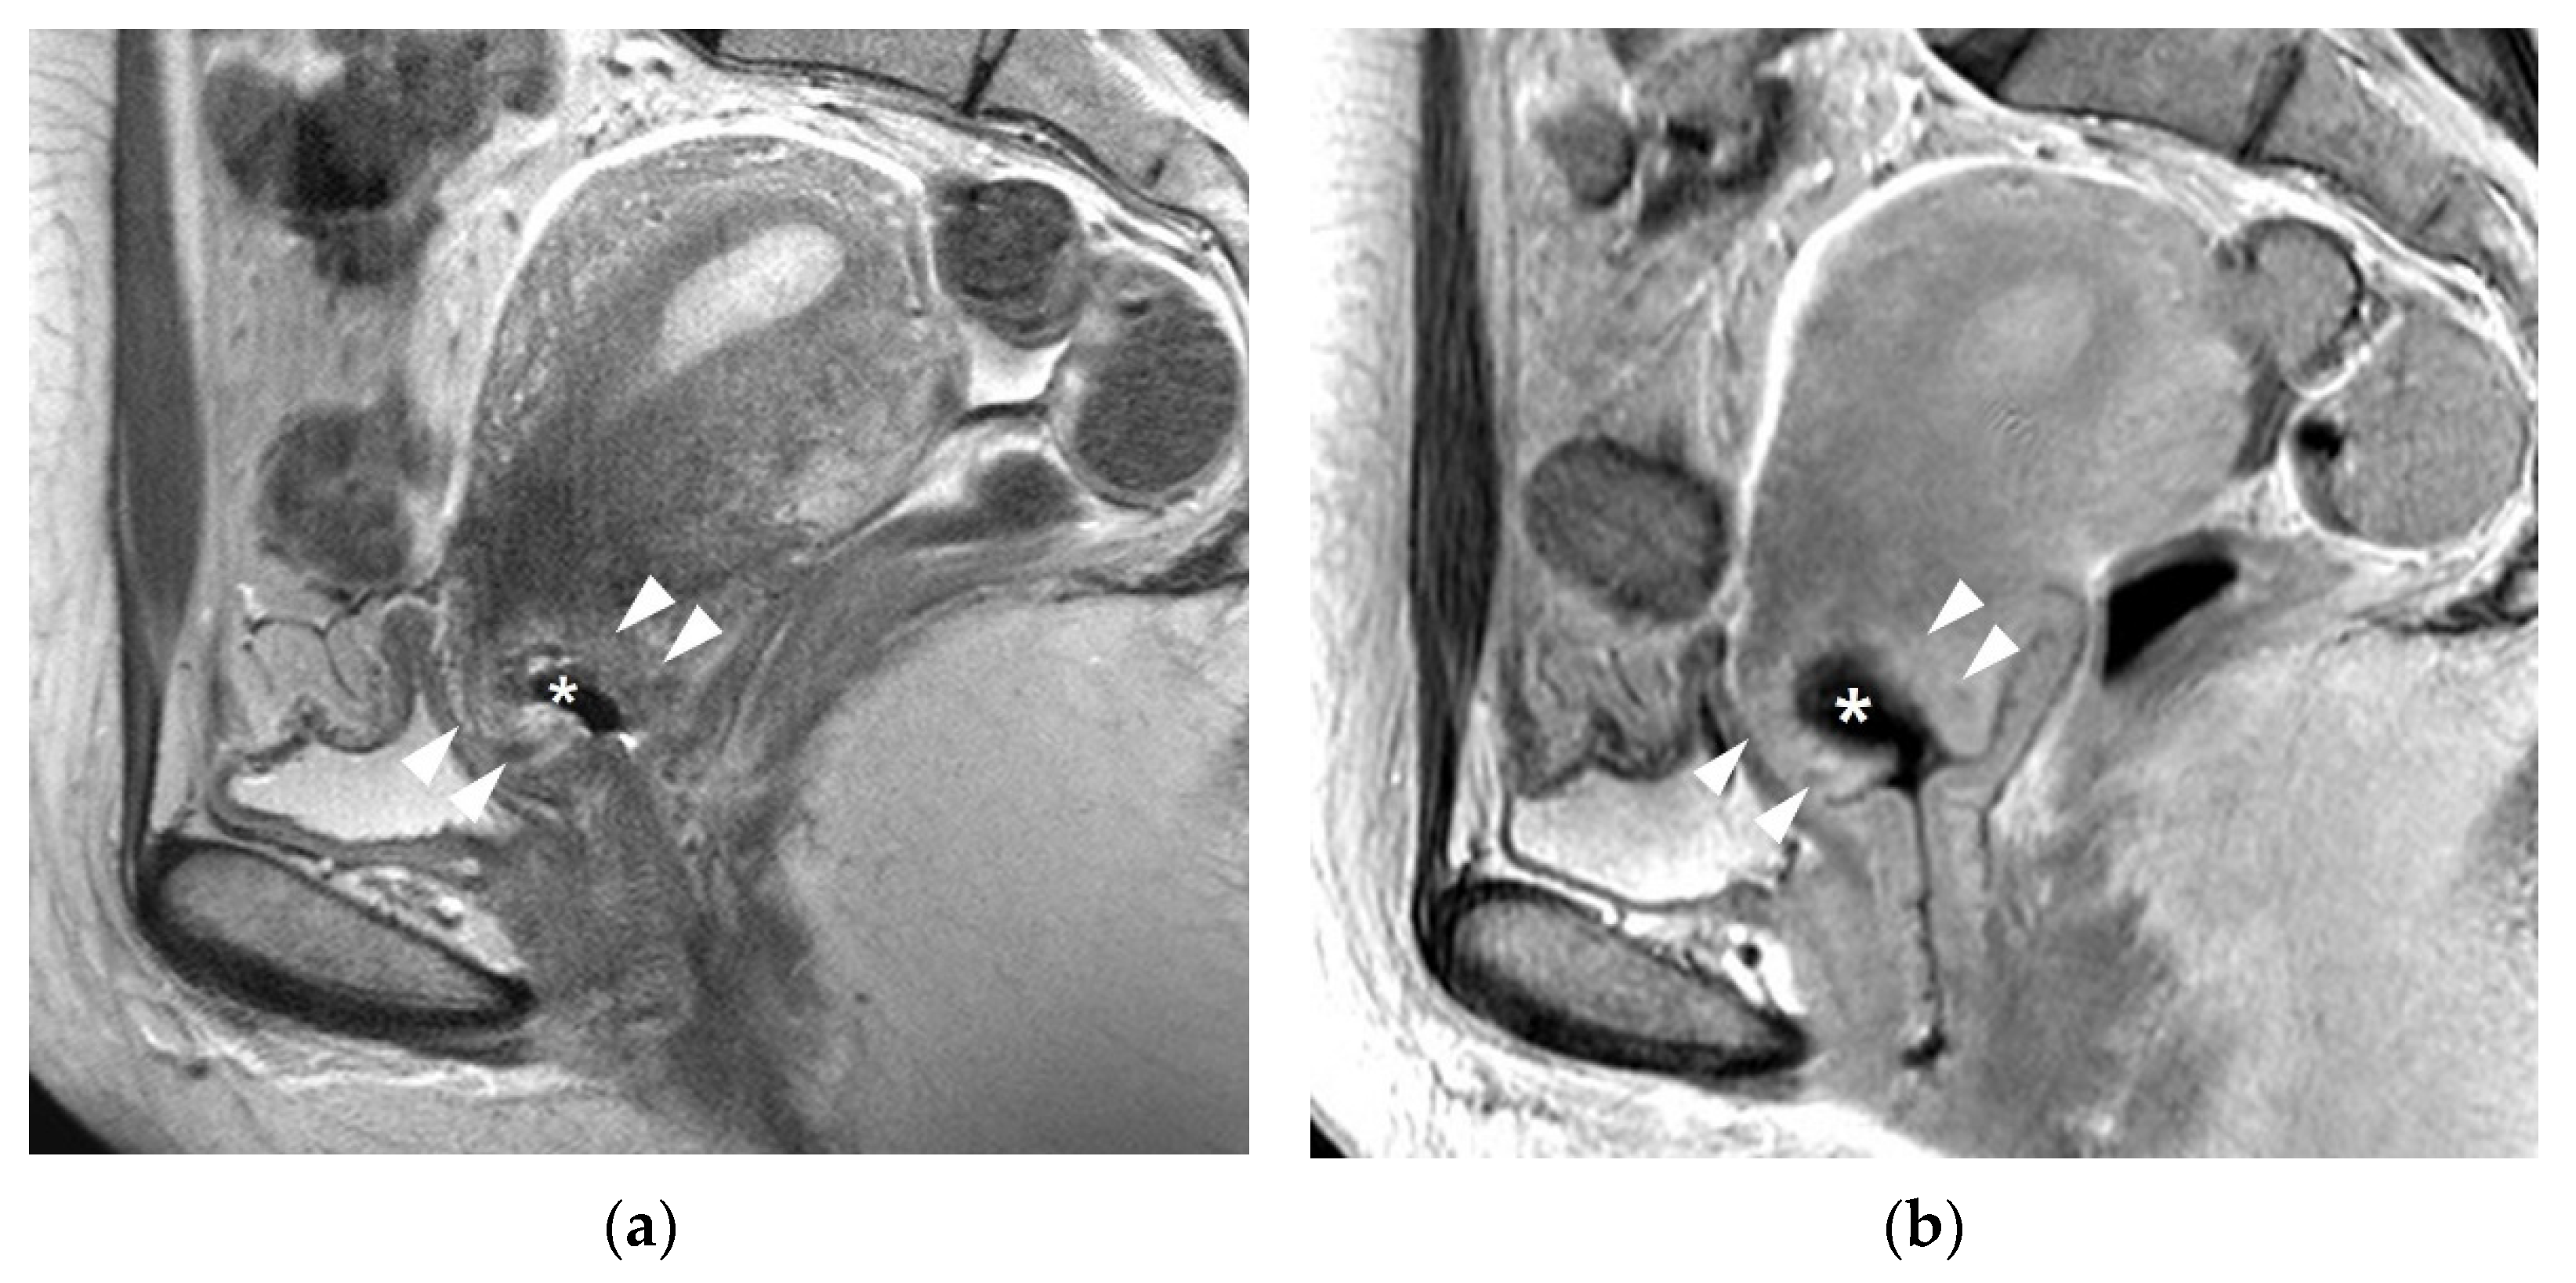

3.1. T2WI Findings